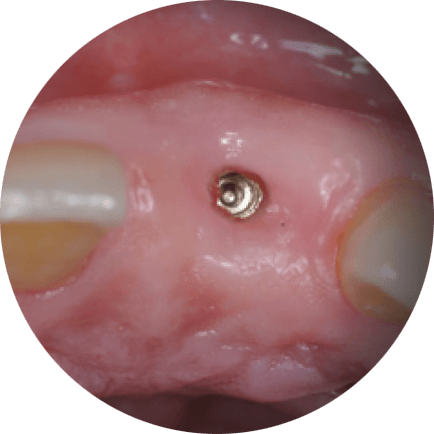

03 —

Implantų pozicionavimas ir restauracijų modeliavimas toleruoja ne didesnę nei 1mm paklaidą

Implantų pozicijos ir galutinės restauracijos toleruoja ne didesnę nei 1mm paklaidą, taip užtikrindamos puikią estetiką ir funkciją.

Implantai įsriegti pagal suplanuotą protokolą

Restauracijos uždėtos pagal suplanuotą protokolą